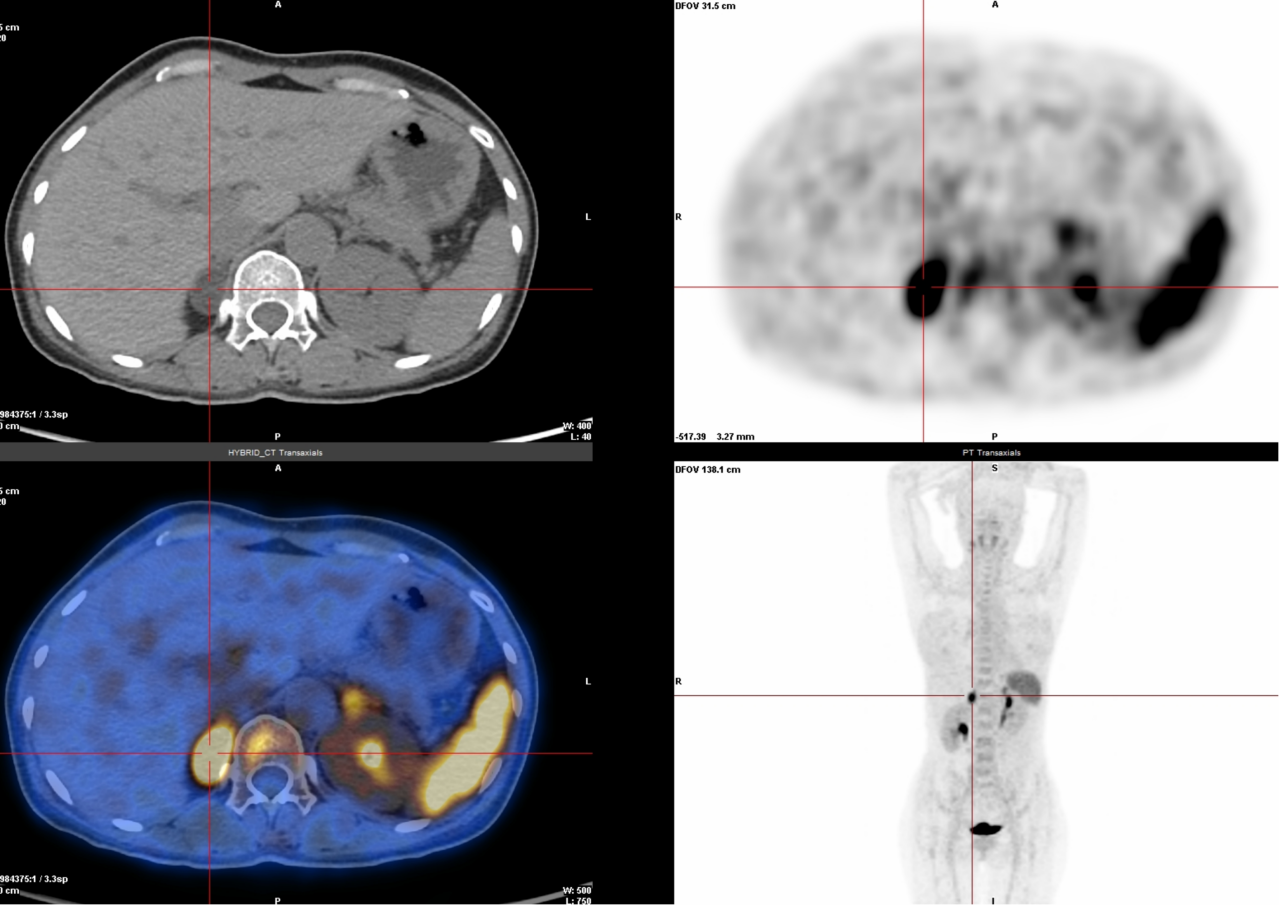

4. 醛固酮瘤、多发性骨髓瘤、惰性淋巴瘤检查(68Ga-Pentixafor):这些肿瘤表面有一种叫CXCR4的“标记物”,这种检查能精准锁定它。

△右侧肾上腺醛固酮瘤